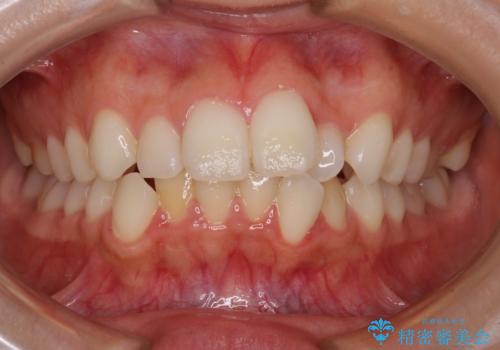

前歯のがたつき 深い噛み合わせを改善したい